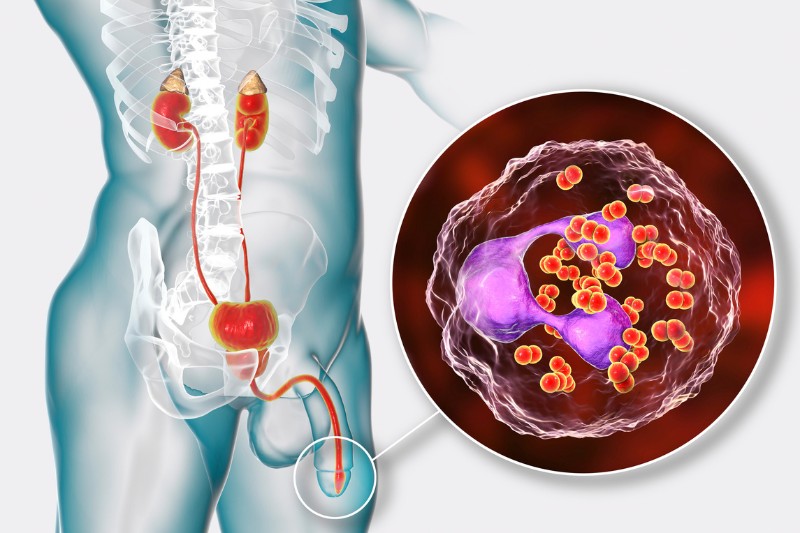

Bệnh lậu là một bệnh truyền nhiễm phổ biến, lây truyền chủ yếu qua đường tình dục, do vi khuẩn Neisseria gonorrhoeae gây nên. Căn bệnh này có thể xảy ra ở cả nam và nữ, ngay cả những đối tượng chỉ quan hệ tình dục lần đầu. Trong đó, một số nhóm người sau sẽ có tỉ lệ mắc bệnh cao hơn cả:

Tương tự như các bệnh lây truyền qua đường tình dục khác, bệnh lậu ở giai đoạn mãn tính có thể ảnh hưởng đến một số cơ quan của cơ thể, nhất là phần niêm mạc ở bộ phận sinh dục và bộ phận có môi trường ẩm ướt như miệng, mắt, niệu đạo, trực tràng, cổ họng, hậu môn, ống dẫn trứng, cổ tử cung và tử cụng. Do đó, cả ba hình thức quan hệ tình dục bao gồm quan hệ qua đường hậu môn, âm đạo và miệng đều có khả năng lây nhiễm bệnh lậu.

Phụ nữ mang thai nếu mắc bệnh lậu có thể dễ dàng truyền bệnh sang con trong quá trình chuyển dạ. Bởi vì vi khuẩn lậu cư trú nhiều nhất ở cổ tử cung và âm đạo nên khi người mẹ bị lậu, vi khuẩn này có thể lây lan sang thai nhi qua nhau thai, đường nước ối hoặc khi chuyển dạ, thai nhi theo ống dẫn sinh ra ngoài, tiếp xúc với lậu cầu ở cổ tử cung và âm đạo.